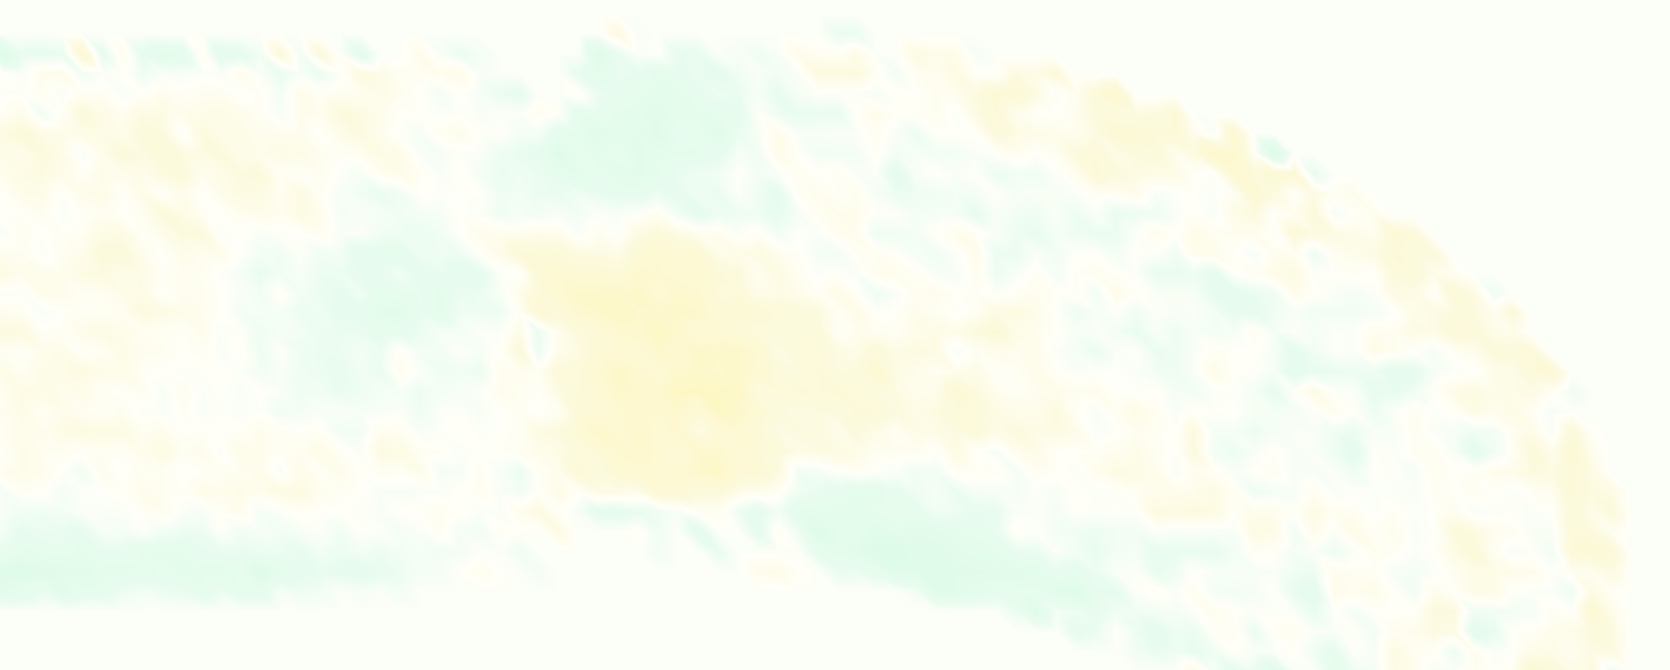

The gross morphology of the model valve that emerged from this process is shown in Figure 4. The free edge was 2.87 cm, corresponding to 3.3 cm in the predicted loaded configuration. After the pinching the leaflets together at the commissures, this left approximately 2.1 cm of free edge rest length per leaflet free to move independently of the other leaflets, within measurement error of ±0.1 cm from the free edge length of 2.2 cm measured on the prostheses. The leaflet rest height was 0.94 cm corresponding to a predicted loaded height of 1.44 cm. The measured leaflet height of 1.3 cm is nearly the predicted loaded height of 1.44 cm, which may be because the leaflets are so compliant in the radial direction, that pulling them flat to measure them achieved substantial stretches. The fiber orientation of the model runs from commissure to commissure and qualitatively matches experimental observations [38], though direct quantitative comparison is beyond the scope of this work. One minor limitation is that we do not add bending rigidity to the leaflets, beyond what emerges from the thickening process described above, and thus may not accurately capture leaflet flutter or other similar behaviors. Based on the thickness of mm, we estimated the mean tangent modulus at the predicted loaded stretches as dynes/cm2 circumferentially and dynes/cm2 radially. The prosthetic valve tissue is fixed in glutaraldehyde, and literature values for the fully-recruited circumferential tangent modulus of fixed porcine aortic valve tissue vary widely. Based on the experimental measurements of Billiar and Sacks and their constitutive law for valves fixed under 4 mmHg of pressure, we evaluated their constitutive law at the relevant stretches and and estimated the circumferential tangent modulus to be dynes/cm2 [6]. Rousseau et al. reported moduli ranging from to dynes/cm2, depending on the applied preload during fixation [36]. Sung et al. reported moduli ranging from to dynes/cm2, depending on fixation pressure [43]. Thus our estimated tangent modulus falls within the range of existing studies, so we considered our resultant modulus in good agreement given the complexity of the steps involved, phenomenological nature of the constitutive law and uncertainties in experiments. We do not have access to the precise material properties of the prosthetic valve, and further, the only literature we could find on the material properties of a similar prostheses reported the tangent modulus at one particular loading, which did not appear to be at a relevant stretch for comparisons with our model [19]. Thus, our model has material properties in a reasonable range for a fixed aortic valve prostheses (placed in the pulmonary position in our simulations), but it does not directly model the material properties of the prostheses.

We constructed the model vessel for FSI simulations from data from the MRI scans (Figure 4). The signal magnitude of 3D printed model material is distinct from the signal of the fluid in the scans, and we applied a thresholding operation to generate a three-dimensional model of the printed vessel surface. Using the MRI data ensured that the MRI and simulation coordinates were consistent in space and there were no alignment or registration errors. While using the files that generated the 3D printed model would have offered more spatial fidelity, the potential error in flow fields due to any mis-registration would have likely been much more substantial. Using Meshmixer (San Rafael, CA), we smoothed the mesh to remove stair-step effects and removed artifacts from the valve scaffold. We then remeshed to the desired edge length of 0.25 mm and extruded the model 0.25 mm and 0.5 mm to create a three-layer structure. As in the valve, this serves to eliminate the “grid aligned artifact” that can occur with pressure differences across thin membranes in the IB method [16]. Flow extenders of length 1 cm were added to the vessel at the inlet and both outlets to ensure that the normal to the vessel was aligned with the normal of the fluid box at the inlets and outlets. In FSI simulations, the vessel was held in place using target points, stiff springs of zero rest length that connect the current position of each model node to its desired position (Section 3.3). Additional linear springs are placed on each edge in the triangulated model. These springs are not meant to model a particular material and only serve to keep the vessel rigid and stationary throughout the simulation.